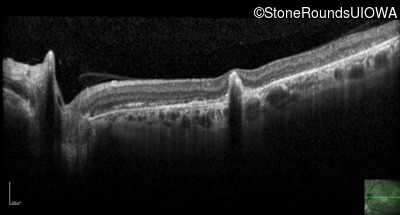

Optical Coherence Tomography - Right - 20/100

Exemplar / OCT Stack

OCT Stack

Optical Coherence Tomography - Left - 20/100

Infrared Fundus Photograph - Right - 20/100

Exemplar

Infrared Fundus Photograph - Left - 20/100